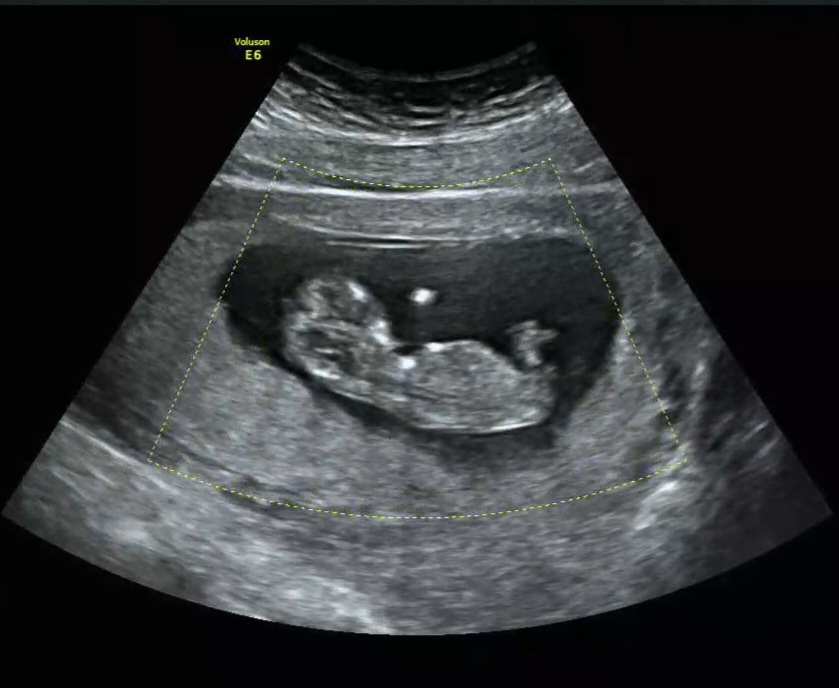

12주차에 찍은 초음파입니다! 아무리 봐도 저는 모르겠습니다,,, 각도법 잘 보시는 분들 알려주세요 ㅠㅠ

딸같아요! 꼬리랑.척추가 평행하네요